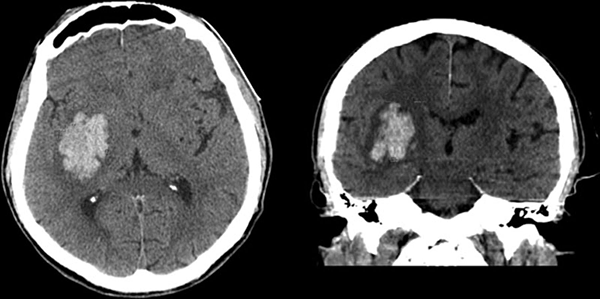

Для установления предварительного диагноза необходимо получить подробую информацию в отношении истории болезни пациента. При постановке диагноза необходимо анализировать радиологические результаты и визуализационные изображения, полученные в ходе проведения компьютерной томографии и магнитно-резонансной томографии. При выборе метода диагностики предпочтение отдается компьютерной томографии из-за возможности точной постановки диагноза в течение короткого времени.

Поскольку симптомы внутримозгового кровоизлияния невозможно отличить от симптомов ишемического инсульта, а методы лечения, тем не менее, противоположны, проведение процедуры визуализации ( КТ или МРТ ) имеет решающее значение для точной и, прежде всего, быстрой диагностики. Как правило, проводится компьютерная томография (КТ) из-за быстроты получения результатов.

Врач может заподозрить кровоизлияние в мозг по типичным симптомам, особенно если есть их связь с травмами или другими факторами риска. Но золотой стандарт диагностики – КТ мозга. В первые сутки после начала кровоизлияния данные будут наиболее точными, даже более значимыми, чем при МРТ. На томограммах свежие гематомы отчетливо видны, врач может определить их точную локализацию, размеры и форму. Кроме того, он сразу же оценивает, насколько пострадали структуры мозга, оболочки и система циркуляции ликвора.

• Неконтрастная компьютерная томография.

□ Внутримозговое кровоизлияние с гематомой правой теменно-затылочной области, левосторонняя гемиплегия (11:20, 17.03.2020). Гипертоническая болезнь. [I61.1]